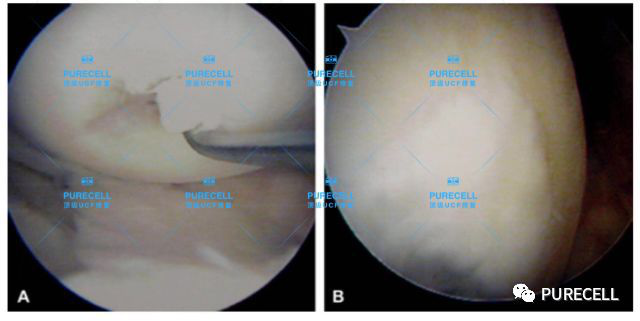

PURECELL首席科學家以及運動醫療專家已經驗證了UCF對膝關節修復的有效性,下圖是UCF軟骨及半月板修復前後影像對比。

它可以改善膝關節內環境,有效激活幹細胞靶向修復膝關節組織,修復韌帶損傷、半月板損傷,修復軟骨及髕骨等組織,能有效減少軟骨受損、骨刺等所帶來的疼痛,並且有效避免了軟骨半月板等膝關節組織的持續磨損和惡化,從根源上改善膝關節疼痛等問題給生活帶來的困擾。